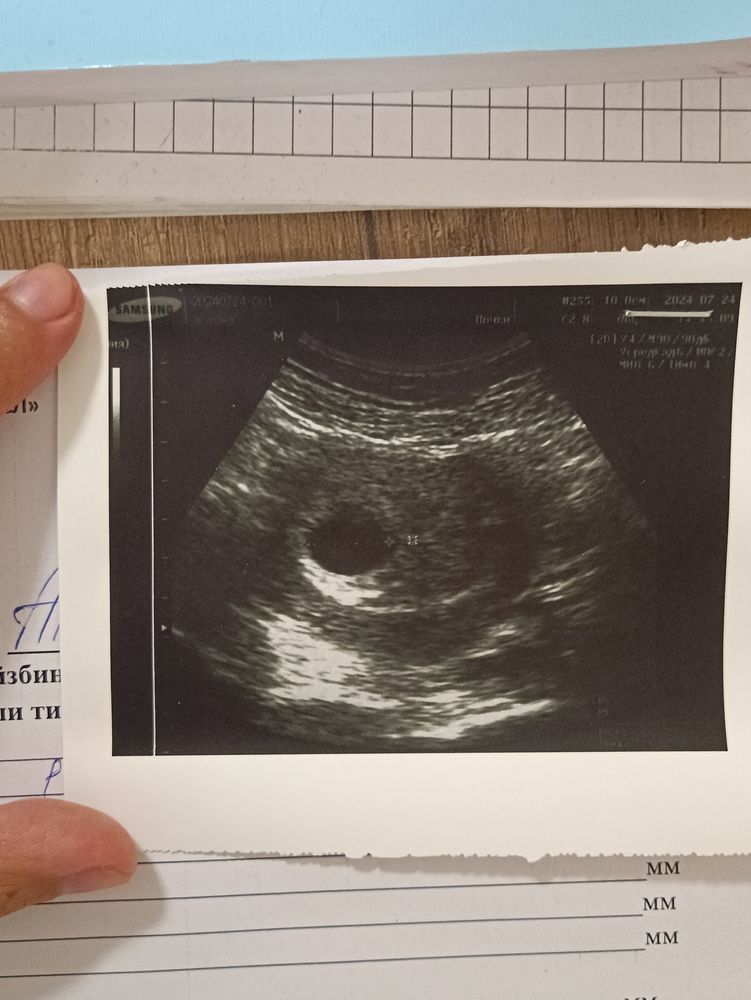

Сегодня 24.07 была на УЗИ. Сказала чтобы сделали абдоминально.Чувствую попала я к так себе врачу. Спонтанно пошла. Она чсс+ поставила. И написала вдпя 10. Если это диаметр плодного яйца, то получается не соответствует сроку. А срок она поставила по моим словам. Акушерских 8 недель. Может вы, что нибудь по снимку сможете понять...

На этом фото ничего не понять,ракурс неудачный и ничего в нем не видно и с таким хгч пя не может быть свд 10,от уровня хгч зависит размер пя у вас ещё 18.07 хгч был 32 тысячи,за 6 дней явно ещё подрос и пя большое по УЗИ должно быть,с хгч 32 тысячи оно уже 15 -18 мм,а у вас ещё 6 дней от хгч прошло,не может пя отставать от срока с хорошим хгч, отстает оно когда хгч растет медленно,но это не ваш случай, сделайте УЗИ трансвагинально и в нормальном месте

В 8 недель уже эмбрион должно быть видно, а у вас видно только ПЯ

И по размерам примерно 10мм соответствует 5 неделям